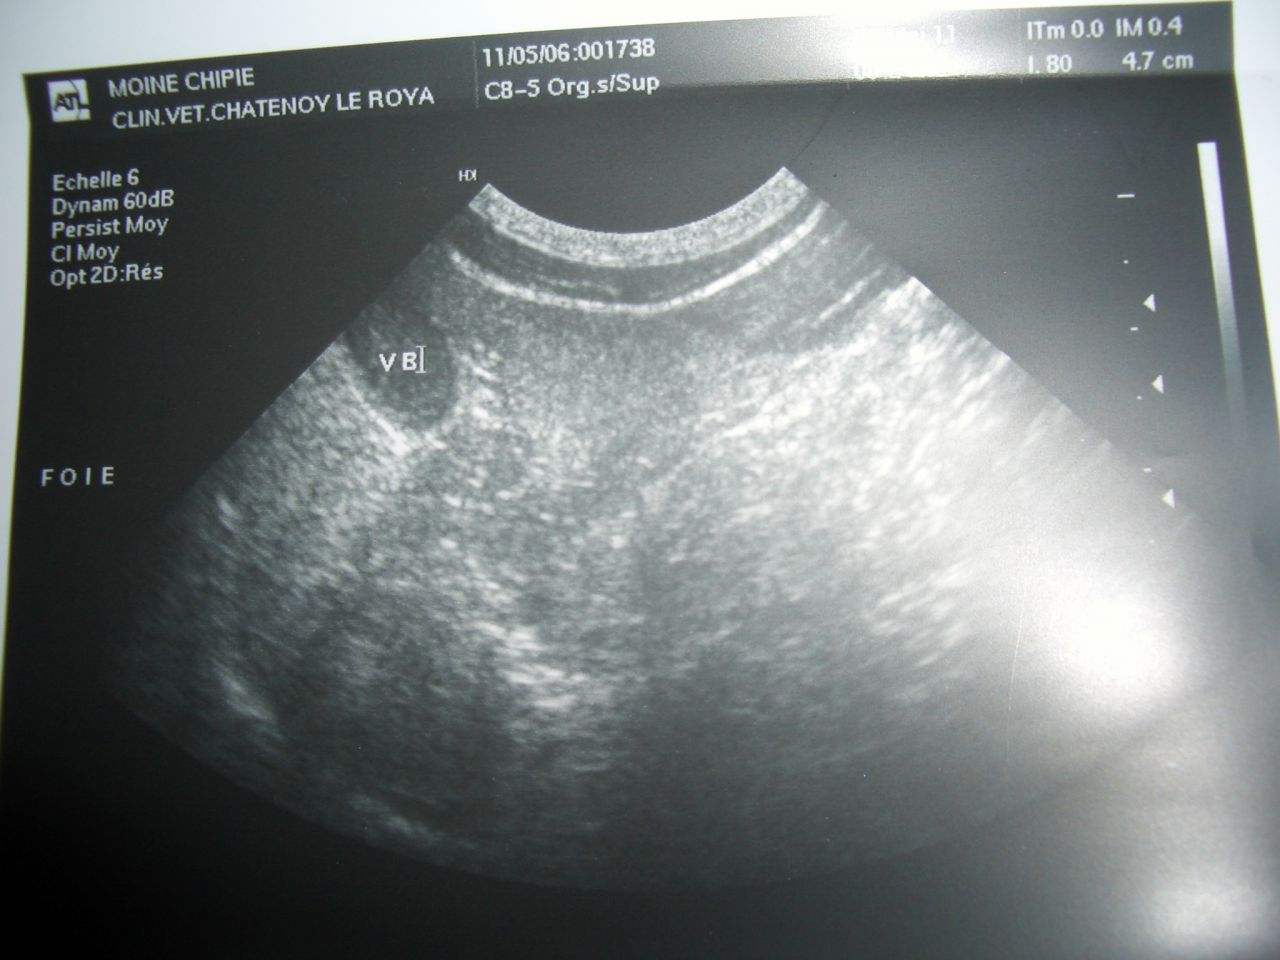

| Dire merci | alors, elle a remangé encore un peu ce matin... elle a du boire 1 gamelle entiére d'eau dans la nuit, les urines sont normales, mais toujours pas de solides dans la litiére. visiblement, c'est normal, le temps que le transit refonctionne normalement. elle fait encore plus vive qu'hier soir, ce matin elle a ralé pour la prise de cachets, mais bon, les 5 comprimés sont avalés et elle ne les a pas vomis.... donc j'éspére que ça va continuer comme ça..... je la pése demain pour voir si elle a grossit un peu et je reprend sa température... donc, dimanche, la pesée:2.5kg température:37.7 (normalement, 38.5) pour ceux qui connaissent un peu, je vous la photo de son echo(foie trop gros) mais moi je voie pas grand chose... et une de sa prise de sang, bin, ça, c'est impressionnant, y'a du rouge partout.. ![]() ![]() |